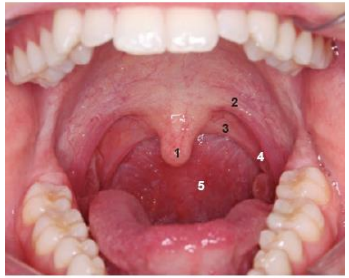

O palato mole contém músculos e tecido fibroso revestidos por mucosa. Durante a deglutição, o palato mole se eleva, evitando a entrada de alimento na parte nasal da faringe. Na fonação, ele pode elevar-se mais ou menos, causando um velamento total ou parcial da boca em relação à parte nasal da faringe, a depender do tipo de som emitido (som nasal ou vocálico)

Levando em consideração a estrutura bucal, analise a imagem e estabeleça a relação com a denominação e número:

A sequência CORRETA é: